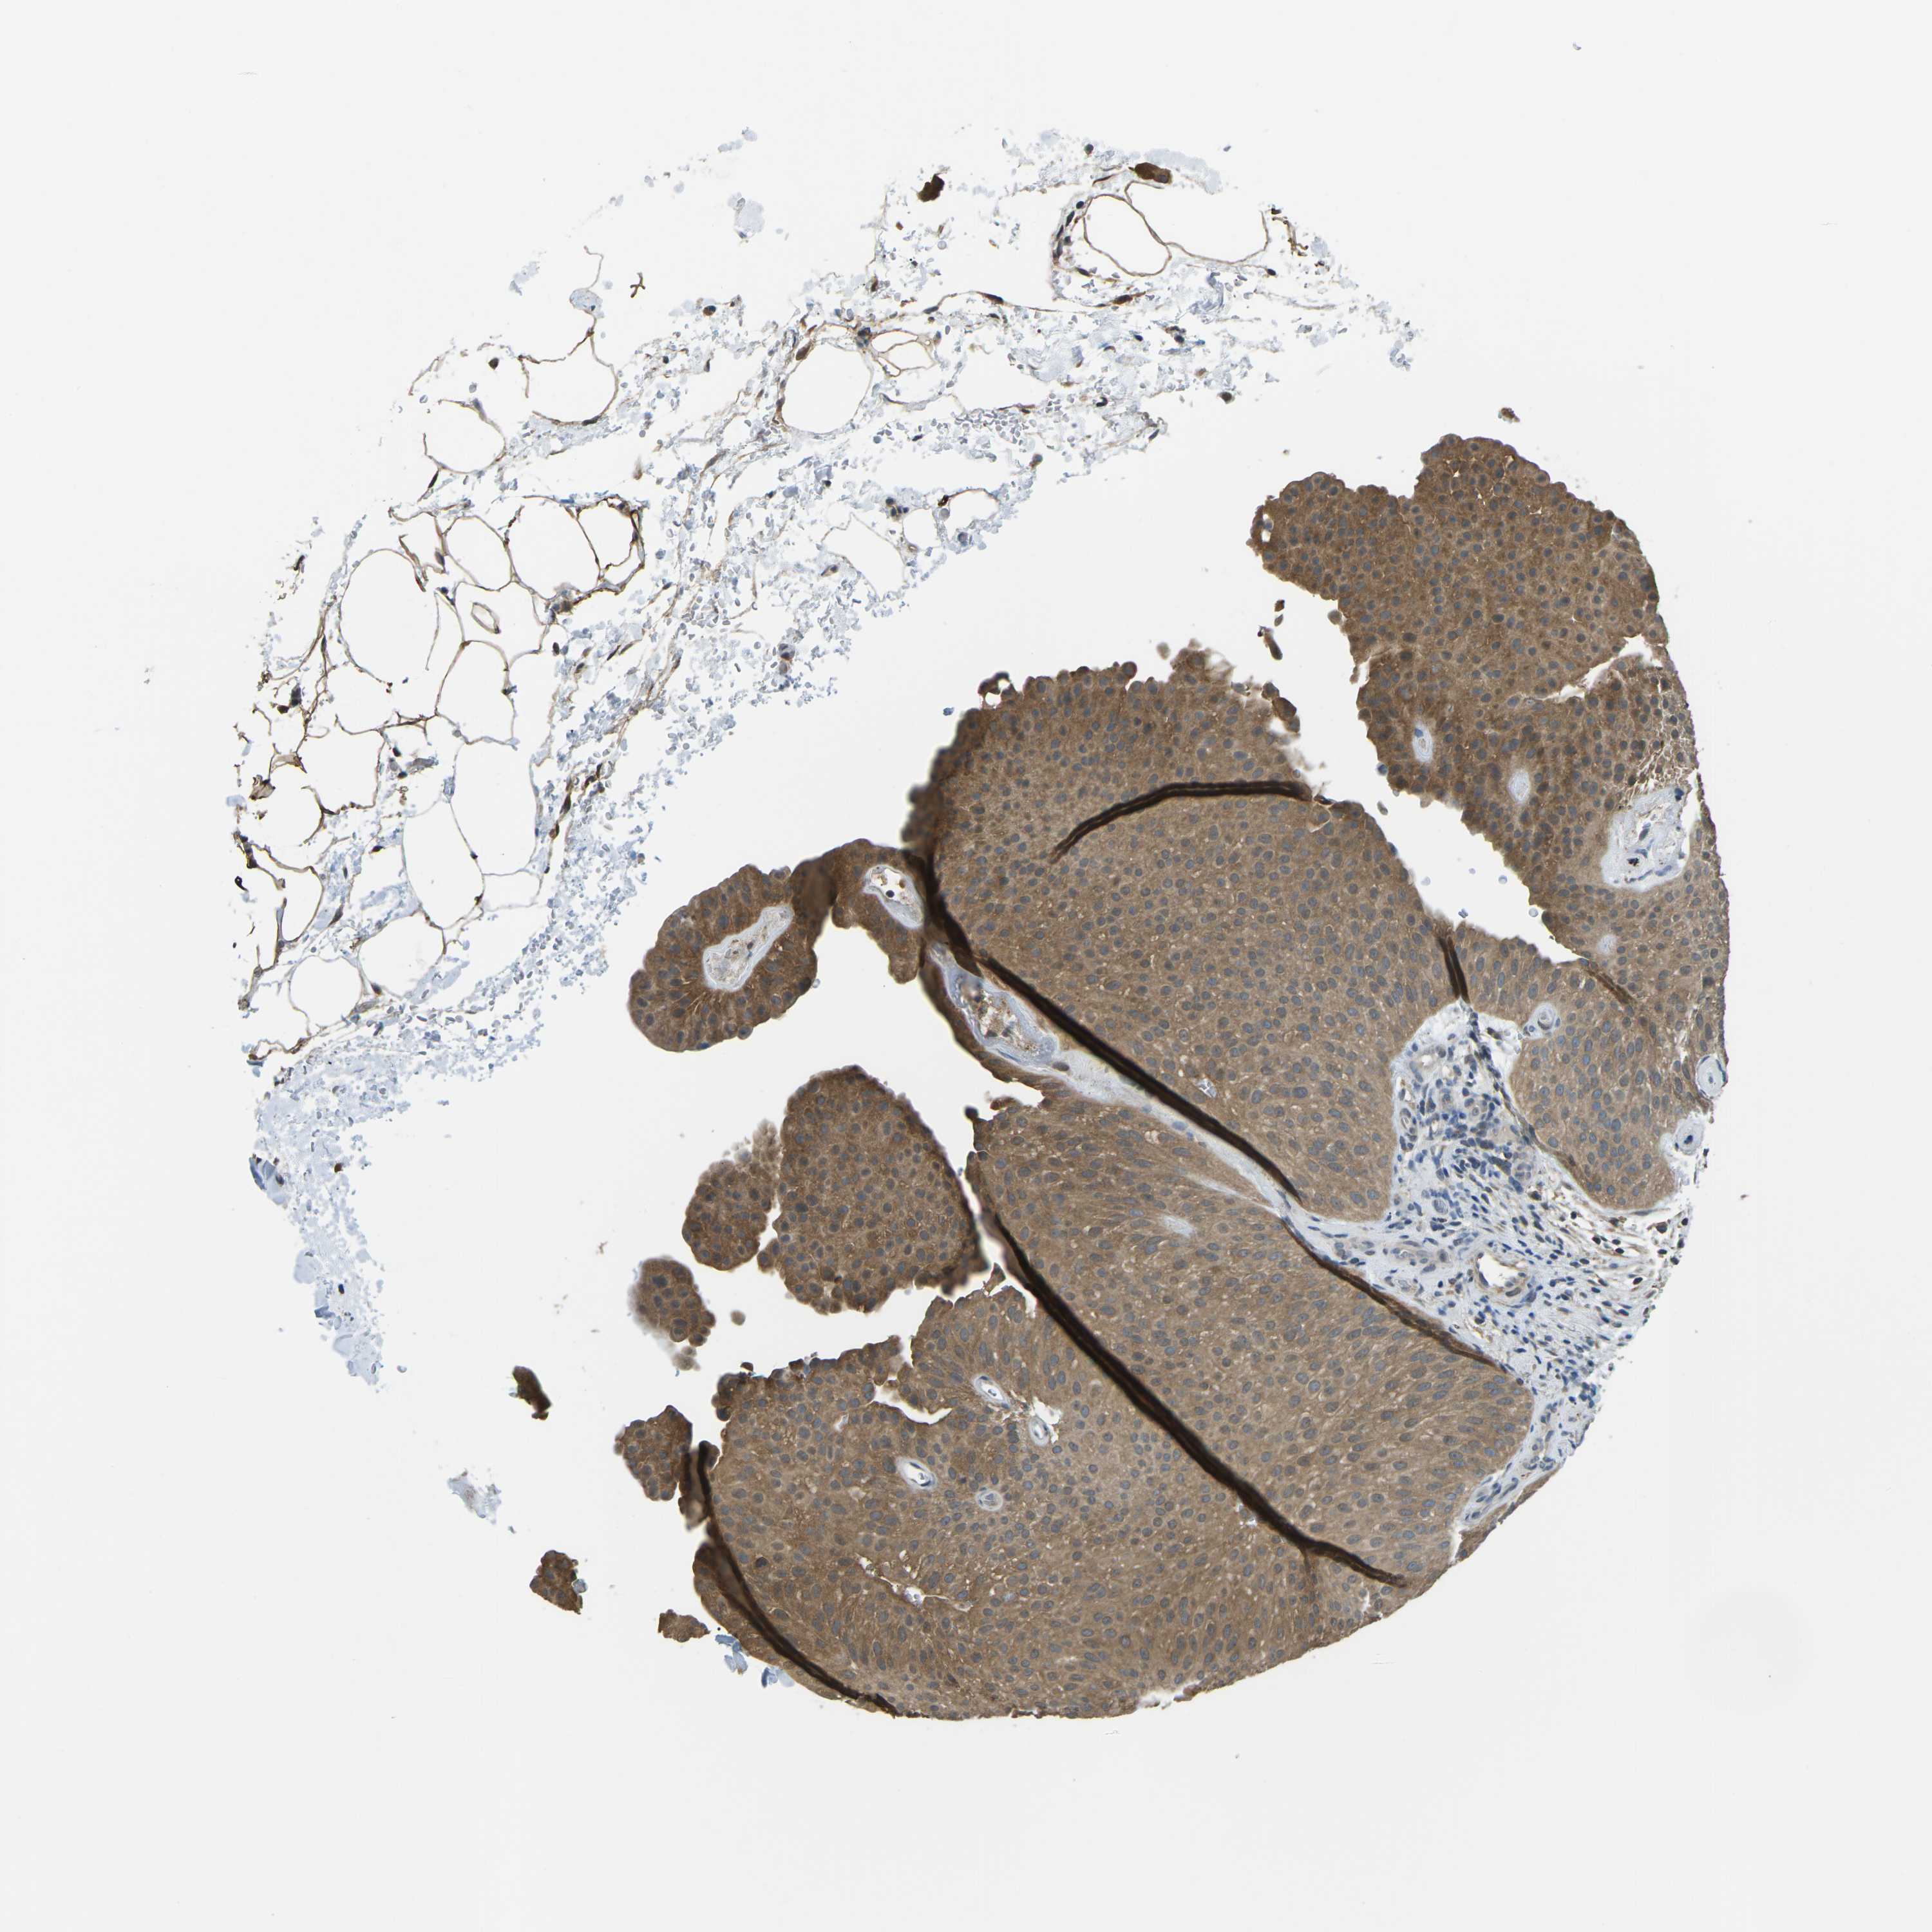

UROTHELIAL CANCER - Protein expressioni

A mouse-over function shows sample information and annotation data. Click on an image to view it in a full screen mode. Samples can be filtered based on level of antibody staining by selecting one or several of the following categories: high, medium, low and not detected. The assay and annotation is described here.

Note that samples used for immunohistochemistry by the Human Protein Atlas do not correspond to samples in the TCGA dataset.

Antibody stainingi

Antibody staining in the annotated cell types in the current human tissue is reported as not detected, low, medium, or high, based on conventional immunohistochemistry profiling in selected tissues. This score is based on the combination of the staining intensity and fraction of stained cells.

Each image is clickable and will lead to virtual microscopy that enables deeper exploration of all samples and also displays staining intensity scores, fraction scores and subcellular localization as well as patient and tissue information for each sample.

Antibody HPA015986

Antibody HPA031974

Antibody HPA040616

Urothelial carcinoma, Low grade

Urothelial carcinoma, High grade